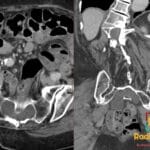

- Radiology Cases: Images with a to-the-point discussion highlighting the specific diagnostic criteria.

Latest Radiology Cases